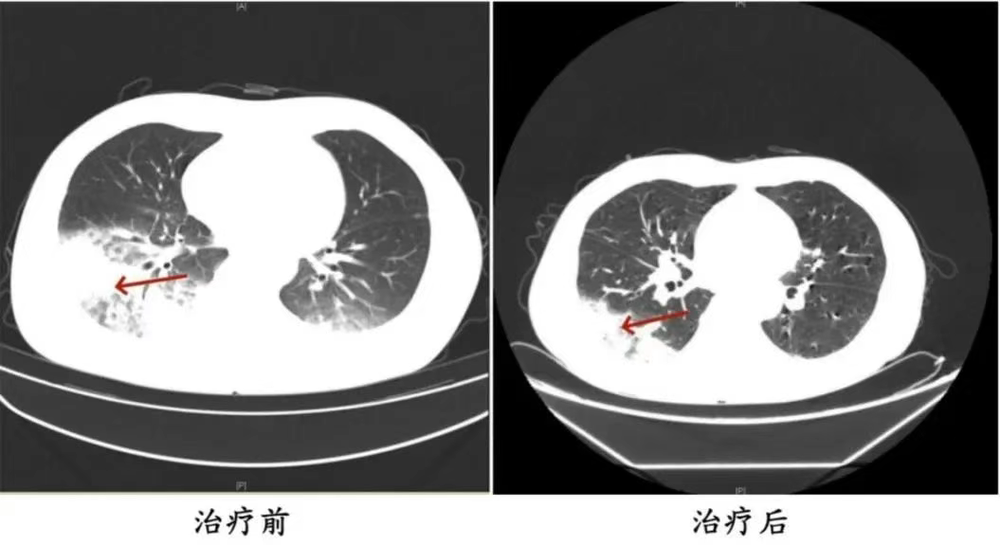

医生询问发现,周先生此前驾车出差,因为天气热,他启动了久未清洗的车载空调,每天在车上的时间超过十个小时,回来后就出现了如上症状。经过检查,最终确诊为军团菌肺炎。

△周先生治疗前后的肺部CT影像